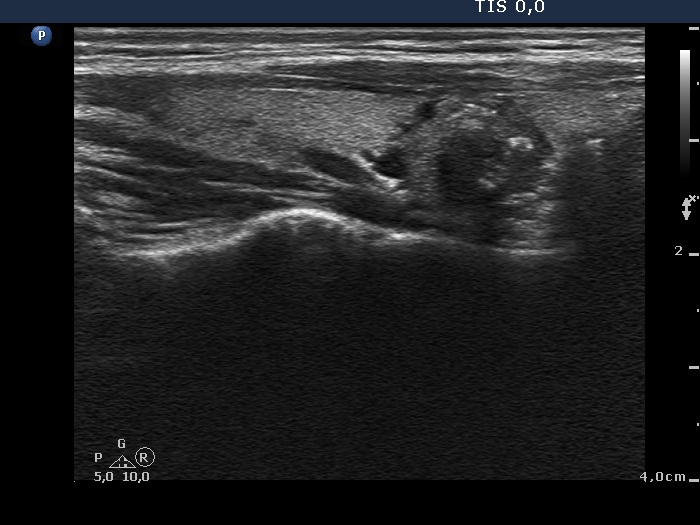

Ultrasonography. The thyroid was echonormal and contained multiple nodules including a hypoechogenic one in the lower pole of the right lobe presenting coarse calcifications. The nodule in the lower part of the left lobe was also noteworthy.

Cytology was performed form the nodule presenting microcalcifications and from that located in the lower pole of the left lobe. The latter resulted in benign colloid goiter while the cytology of the right nodule corresponded to a follicular tumor.

The common ultrasound-cytological diagnosis of the nodule in the right lobe was benign follicular proliferation.

Comment. Although tht cytological pattern of the right lesion corresponds to a follicular tumor if we consider the ultrasound presentation than the risk of a follicular neoplasia is very low: the lesion exhibited neither halo sign nor perinodular bloodf flow. It means that there were not present any signs of a capsule. In such cases the risk of a follicular tumor is less than 5%.